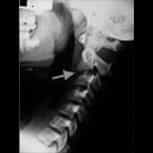

我們是一家位於西班牙巴塞隆納的國際專科醫療中心,不設分院,專注於精準且高品質的醫療照護。我們採用微創手術從病因治療Arnold-Chiari I型症候群、特發性脊髓空洞症與脊柱側彎等相關疾病,致力於為來自世界各地的患者帶來更安全、更有效的治療選擇。

填寫免費終絲疾病遠距咨詢:Chiari畸形第一型、原發性脊髓空洞症、原發性脊柱側彎、顱底凹陷、扁平顱底、齒狀突畸形、腦幹扭結症